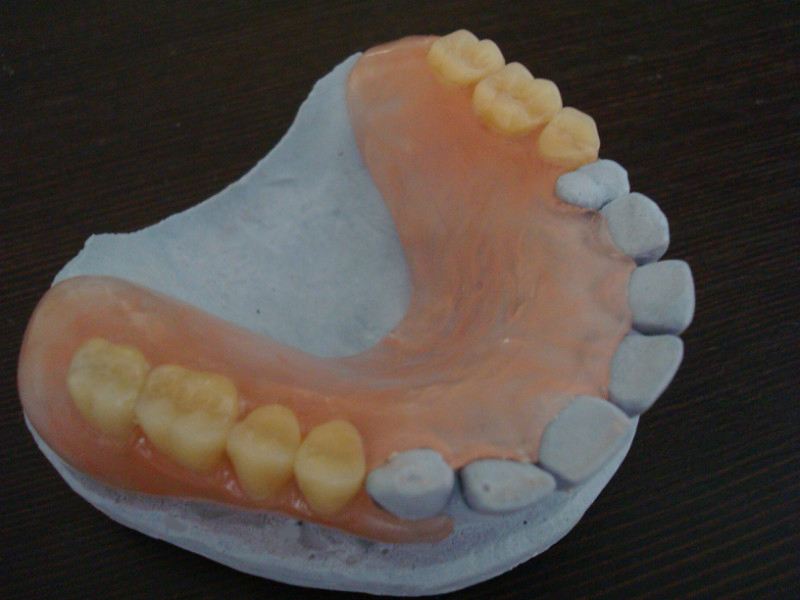

Мини-импланты – это искусственные зубные корни в форме конуса с резьбой по всей длине. В верхней части имплантов расположена головка шаровидной формы, на протезе установлены замки кольцевидной формы, в которые вщелкивается протез (это условно-несъемная технология, а такой протез на имплантах называют еще покрывным). Мини-имплантация показана в случаях, когда нет возможности применения классических корневидных имплантатов. Форма и материал таких имплантатов ничем не отличаются от стандартных имплантатов, но они намного (в 4 раза) тоньше и короче. Их диаметр составляет всего 1,8 мм, поэтому для внедрения мини-импланта в костную ткань нужна маленькая лунка, в большинстве случаев имплантация выполняется транс-гингивально, без разрезов.

Пациент уходит после имплантации уже с протезом. Пример такой операции – здесь.